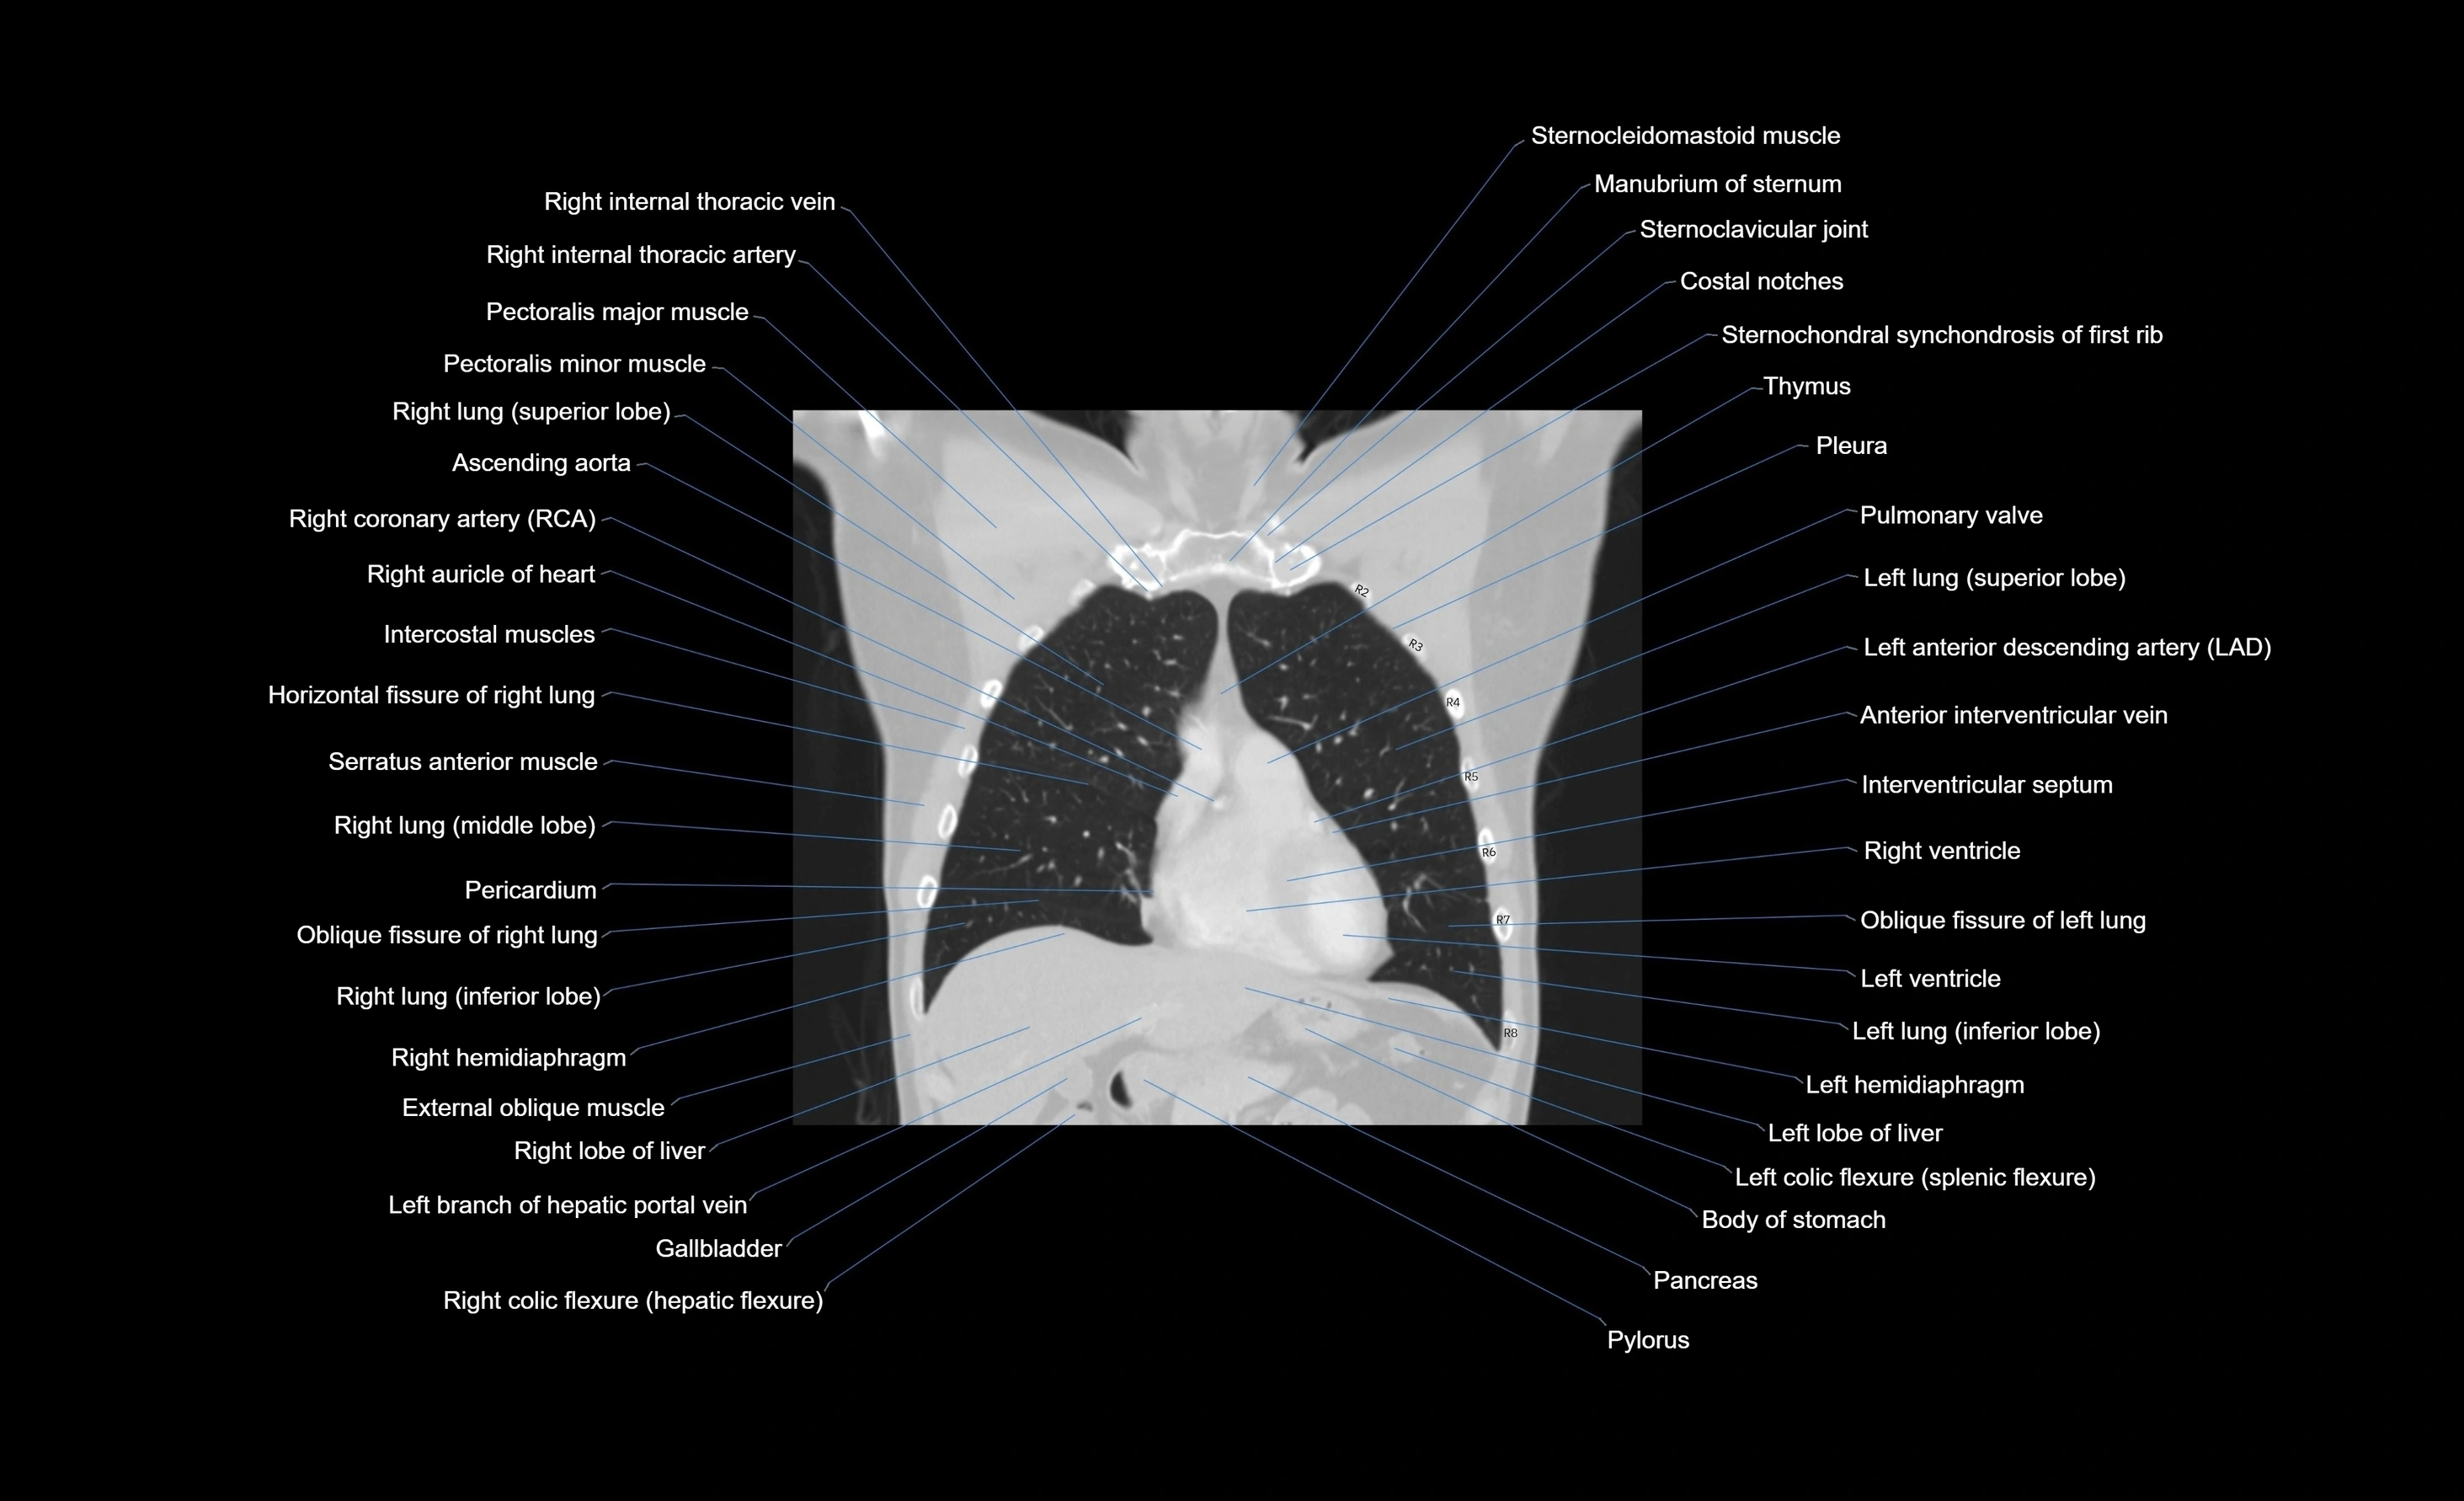

CT images